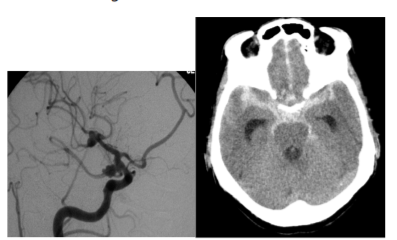

Considere uma paciente feminina, 59 anos, cefaleia inédita súbita de forte intensidade apresentando sonolência com pronto despertar, respondendo adequadamente aos comandos verbais com os seguintes exames de imagens.

É correto afirmar que se trata de: